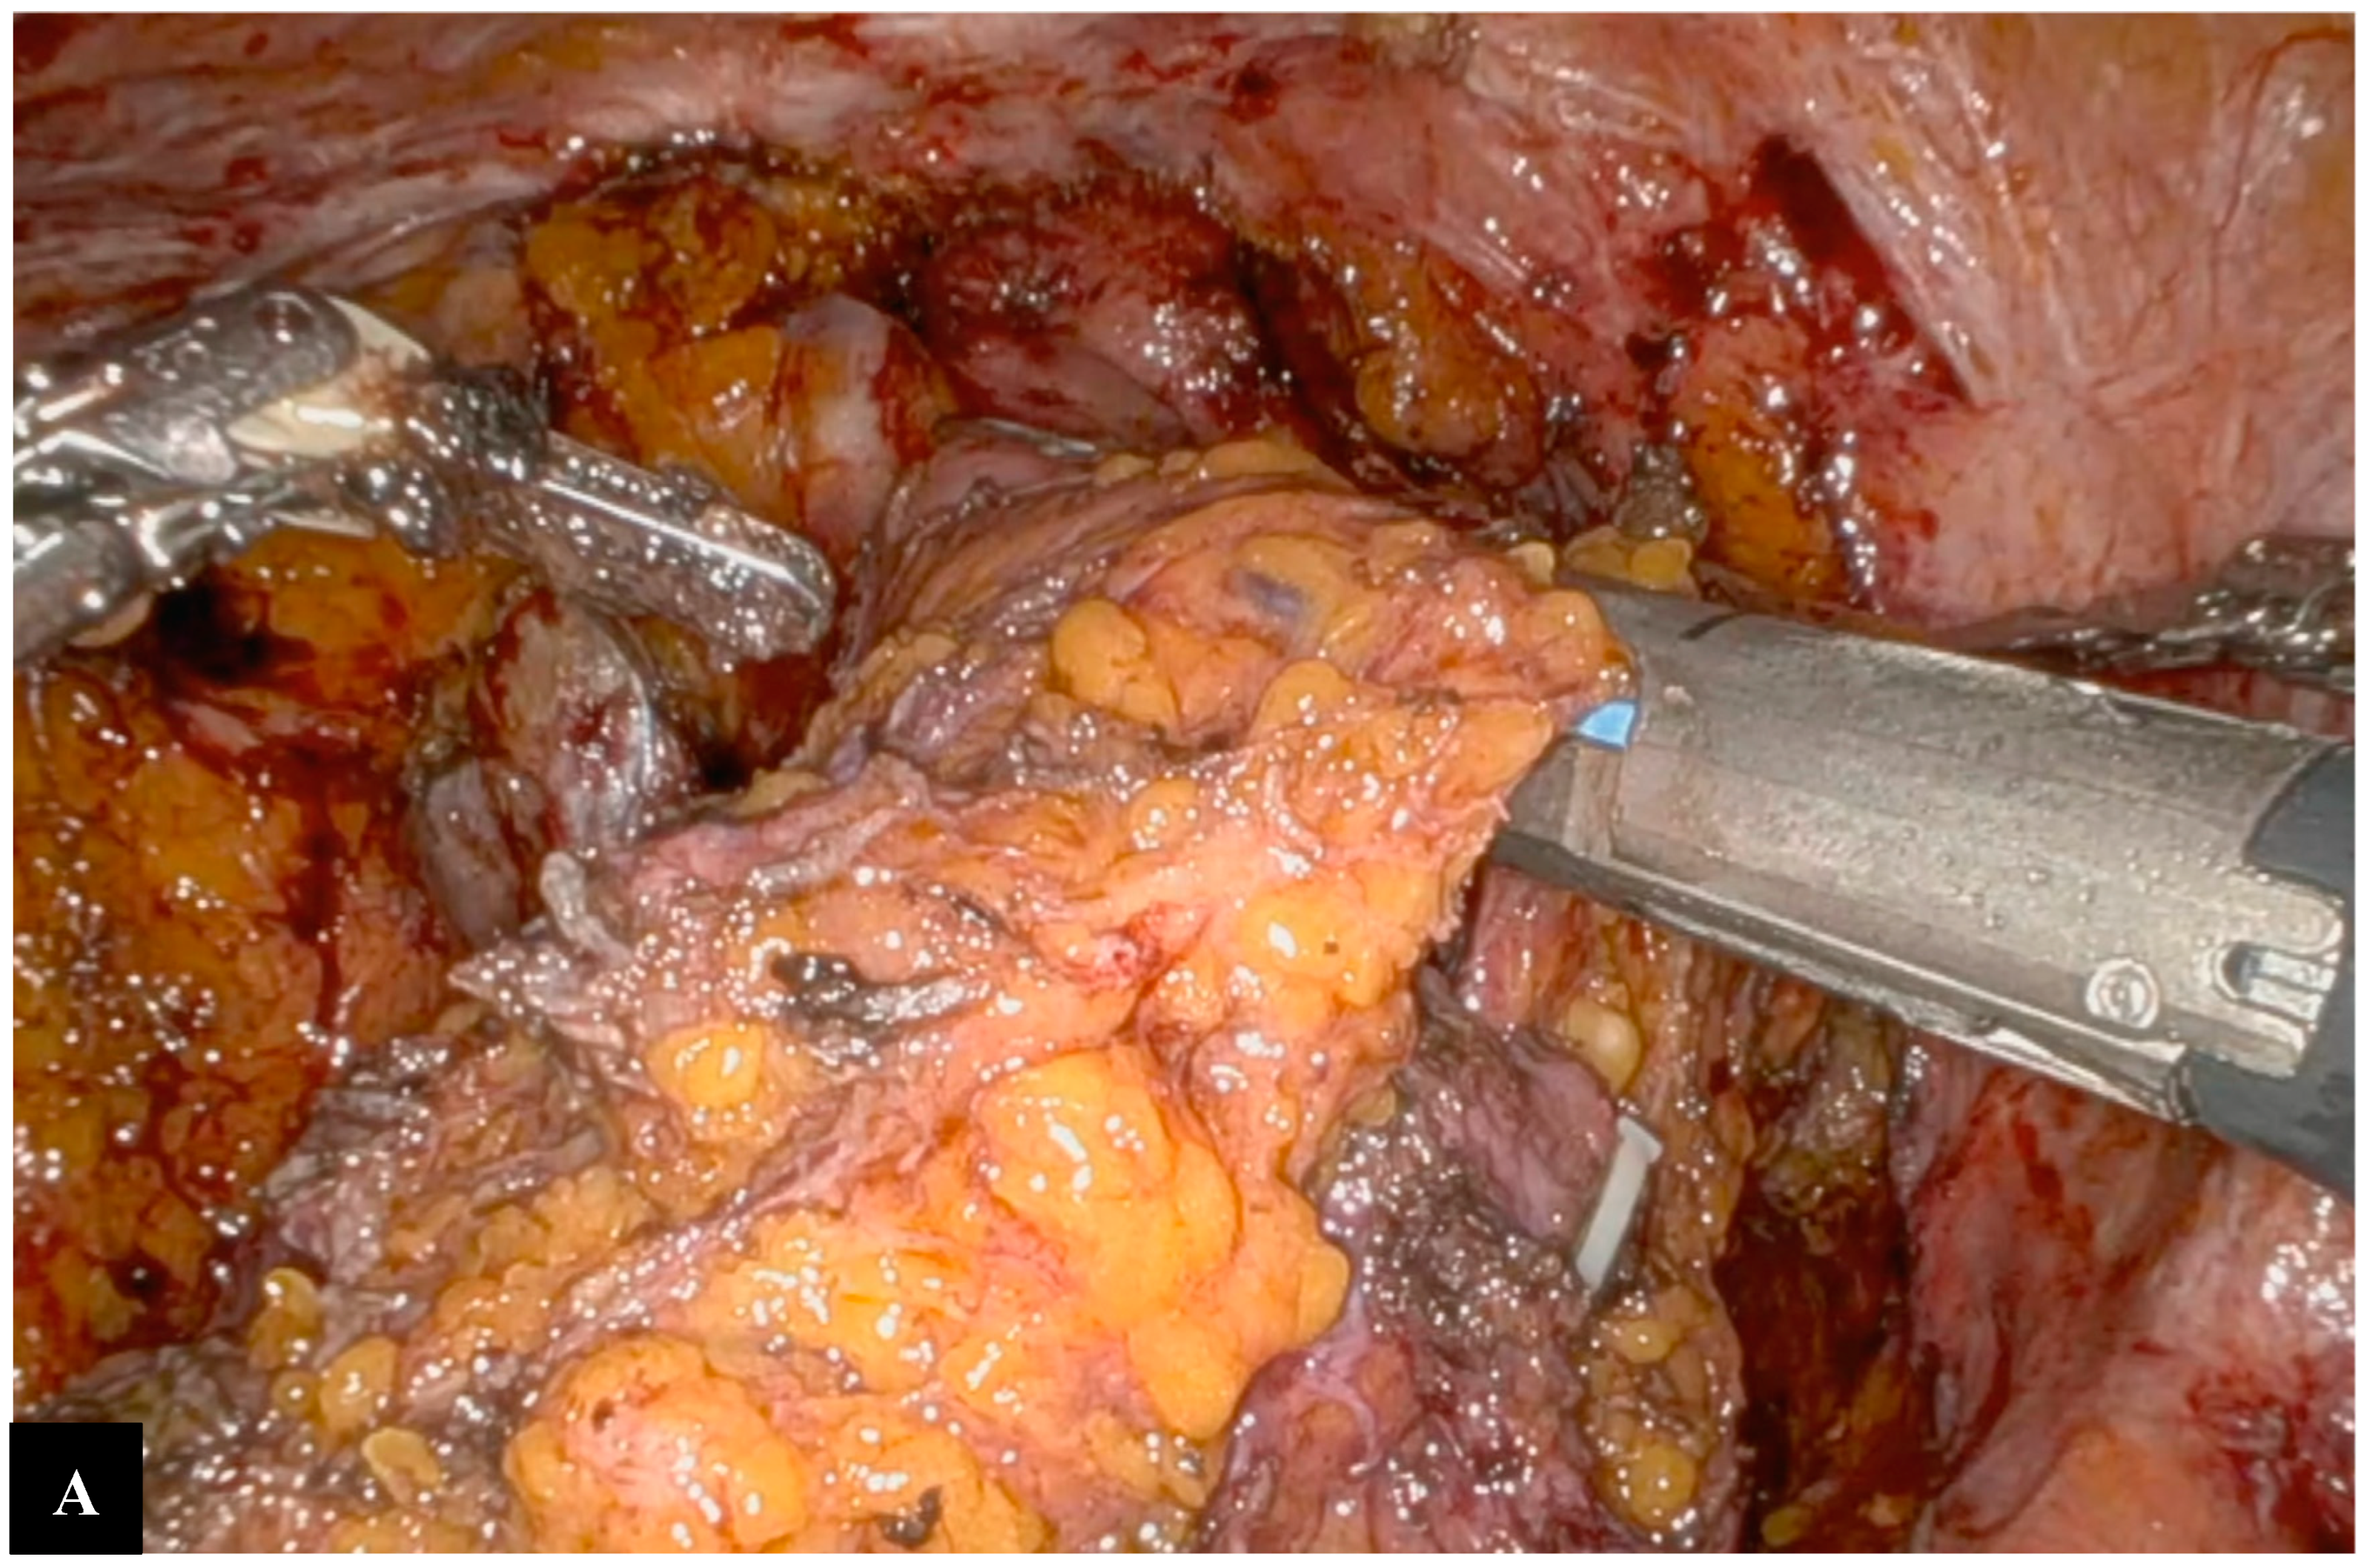

Operative Technique